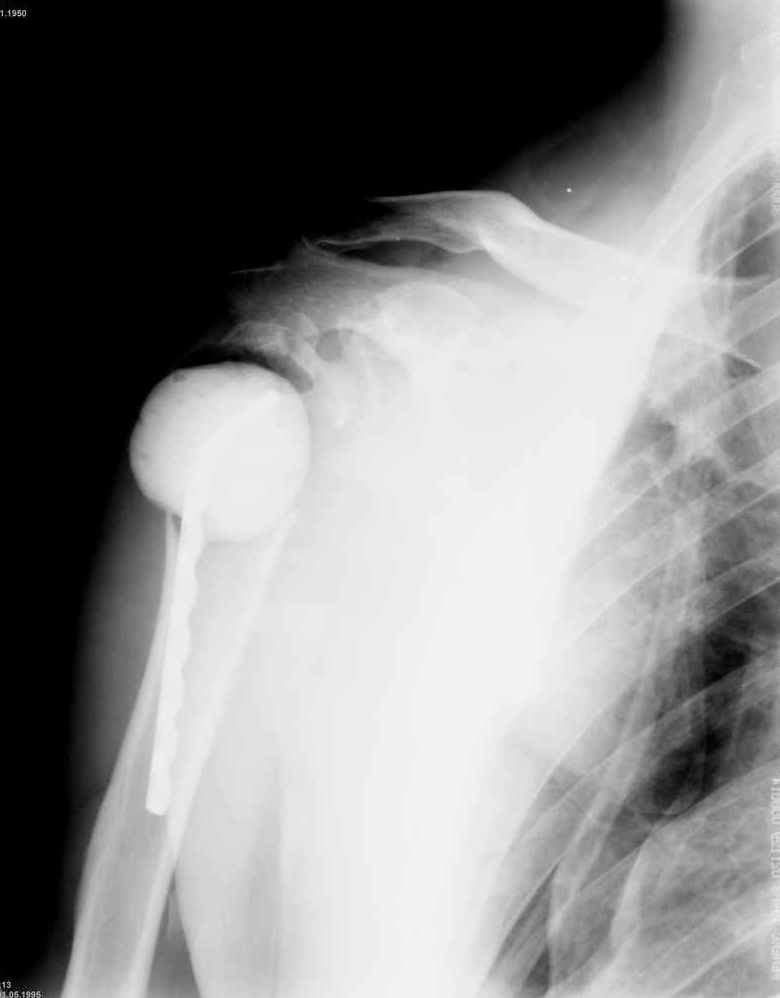

Вложение не в текстовом формате было извлечено…

Имя     : 6.jpg

Тип     : image/jpeg

Размер  : 44848 байтов

Описание: отсутствует

Url     : http://weborto.net:8080/pipermail/ortho/attachments/20070925/75bce6d9/attachment-0013.jpg